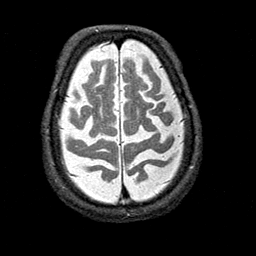

Alzheimer's disease MR T2-weighted -- Slice #39

[Home][Help][Clinical][Tour 1][Tour 2] Slice 39